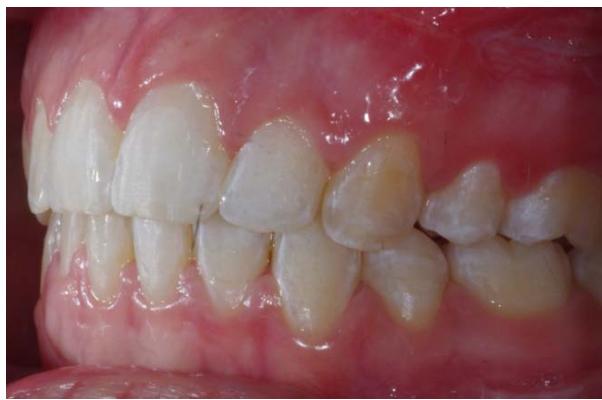

Photos endobuccales de fin de traitement.